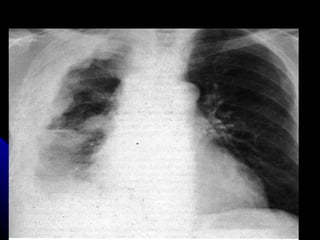

MASA DE MEDIASTINO ANTERIOR TIMOMA

MASA DE MEDIASTINOANTERIOR TIMOMA